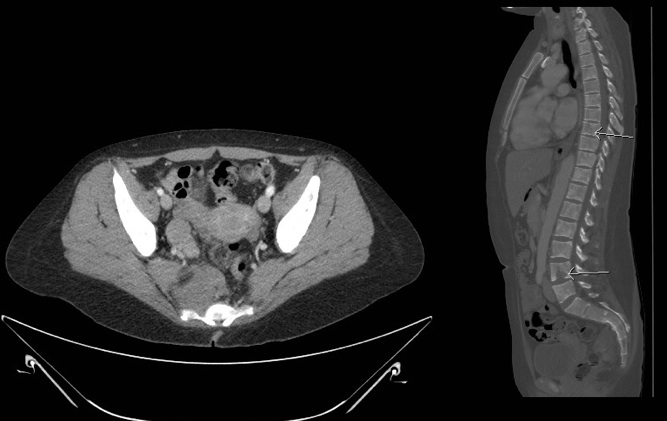

The abdomen and liver should be assessed by CT scan and/or MRI (Figure 4a). A chest CT should be performed if extension of abdominal disease or pulmonary metastasis is suspected. A MIBG scan should be performed to assess bone involvement. If the MIBG scan results are negative, a technetium 99 scan should be performed. Imaging with 123 I-MIBG is optimal for identifying soft tissue and bony metastases and is better than a PET/CT in prospective comparison.[50] If the primary tumor does not take up MIBG, additional imaging of isolated or equivocal positive lesions should be performed.[51] MRI of the spine should be performed to evaluate paraspinal tumors that may extend through neural foramina and compress the spinal cord (Figure 4b).

Figure 4a. Figure 4b.

56mm soft tissue mass in the R pelvis anterior to sacrum, to the Sagittal image of bony lytic lesions

right of the rectum. Soft tissue going into or out of the S4 neural compressing neural foramen.

foramen.